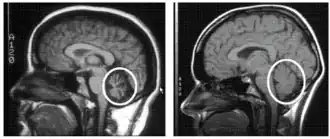

Magnetic resonance imaging scans of two different brains. The scan of the brain on the left indicates a weakened, deteriorated cerebellum of a human with cerebellar degeneration. The scan of the brain on the right indicates a healthy, normally-functioning cerebellum of a human.

To select an appropriate and accurate diagnostic test for cerebellar degeneration, it is crucial that a range of factors specific to each patient are taken into consideration. These include; the patient's age, acuity of their signs and symptoms, associated neurological conditions, and family history of hereditary forms of cerebellar degeneration.[3] A diagnosis for cerebellar degeneration is regarded after any of the aforementioned signs and symptoms surface. For genetically classified forms of cerebellar degeneration, genetic testing can be carried out in order to confirm or deny the diagnosis, where this form of testing is only possible if the gene responsible for the cause of the condition is recognised.[24] In saying this, for most conditions the genetic cause of cerebellar degeneration is unidentified, hence these patients cannot proceed with genetic testing.[1] In cases where cerebellar degeneration is acquired, a diagnosis can be established using imaging methods such as computerised tomography (CT scans) and magnetic resonance imaging (MRI), necessary to detect brain abnormalities in patients with cerebellar degeneration.[25]